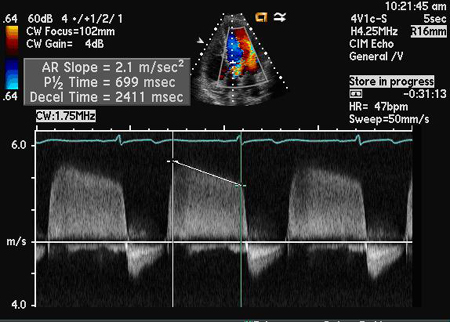

Doppler de onda contínua

Exame

À medida que a RA se agrava, a pressão diastólica do ventrículo esquerdo aumenta rapidamente e a pressão diastólica aórtica diminui rapidamente, acarretando em um tempo de meia-pressão mais curto ou uma inclinação mais abrupta da desaceleração da velocidade. Essas medidas podem ser usadas como parte da avaliação da gravidade da RA.[Figure caption and citation for the preceding image starts]: Doppler de onda contínua do jato regurgitante demonstrando o tempo de meia-pressão da velocidade regurgitante aórticaDos acervos Dr. Sanjeev Wasson e Dr. Nishant Kalra; usado com permissão [Citation ends].

Resultado

pode mostrar tempo de meia-pressão mais curto ou inclinação mais abrupta da desaceleração da velocidade na RA grave